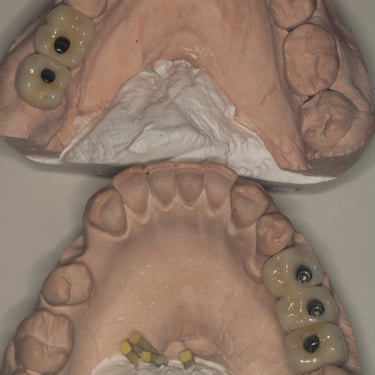

Dentes de porcelana finalizados

Planejamento virtual feito sobre um modelo escaneado da boca do paciente. Fazendo os procedimentos serem de maior precisão.